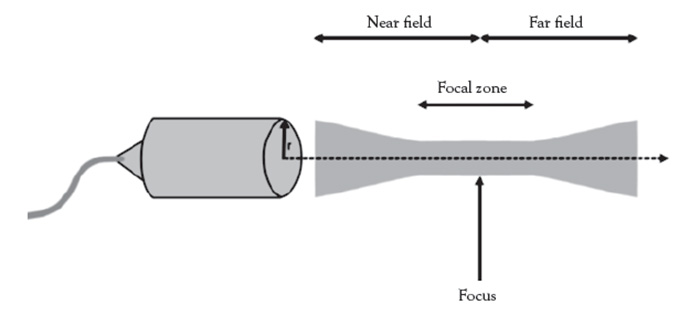

Depth is a modifiable setting set by the user, on the imaging parameter screen. As a general rule, set the depth to 1 cm deeper than the intended target to place the anatomy of interest in the center of the focal zone, where the detail will be seen with the highest spatial resolution [37].

In pre-procedure planning, the use of an ultrasound gel standoff pad is optimal. The device allows optimized detection and specificity of superficial lesions and peripheral vessels that may be otherwise too superficial to visualize. The device places the anatomy of interest deeper into the focal zone (Figure 2), optimizing visualization of the lesion of interest. The technique is particularly useful when using lower resolution ultrasound systems. Currently available aesthetic ultrasound units do not provide power Doppler feature needed to visualize ultra-fine vascular structures, a technology only available on conventional larger complex, expensive state-of-the-art ultrasound imaging systems used in medical clinics and hospital settings.